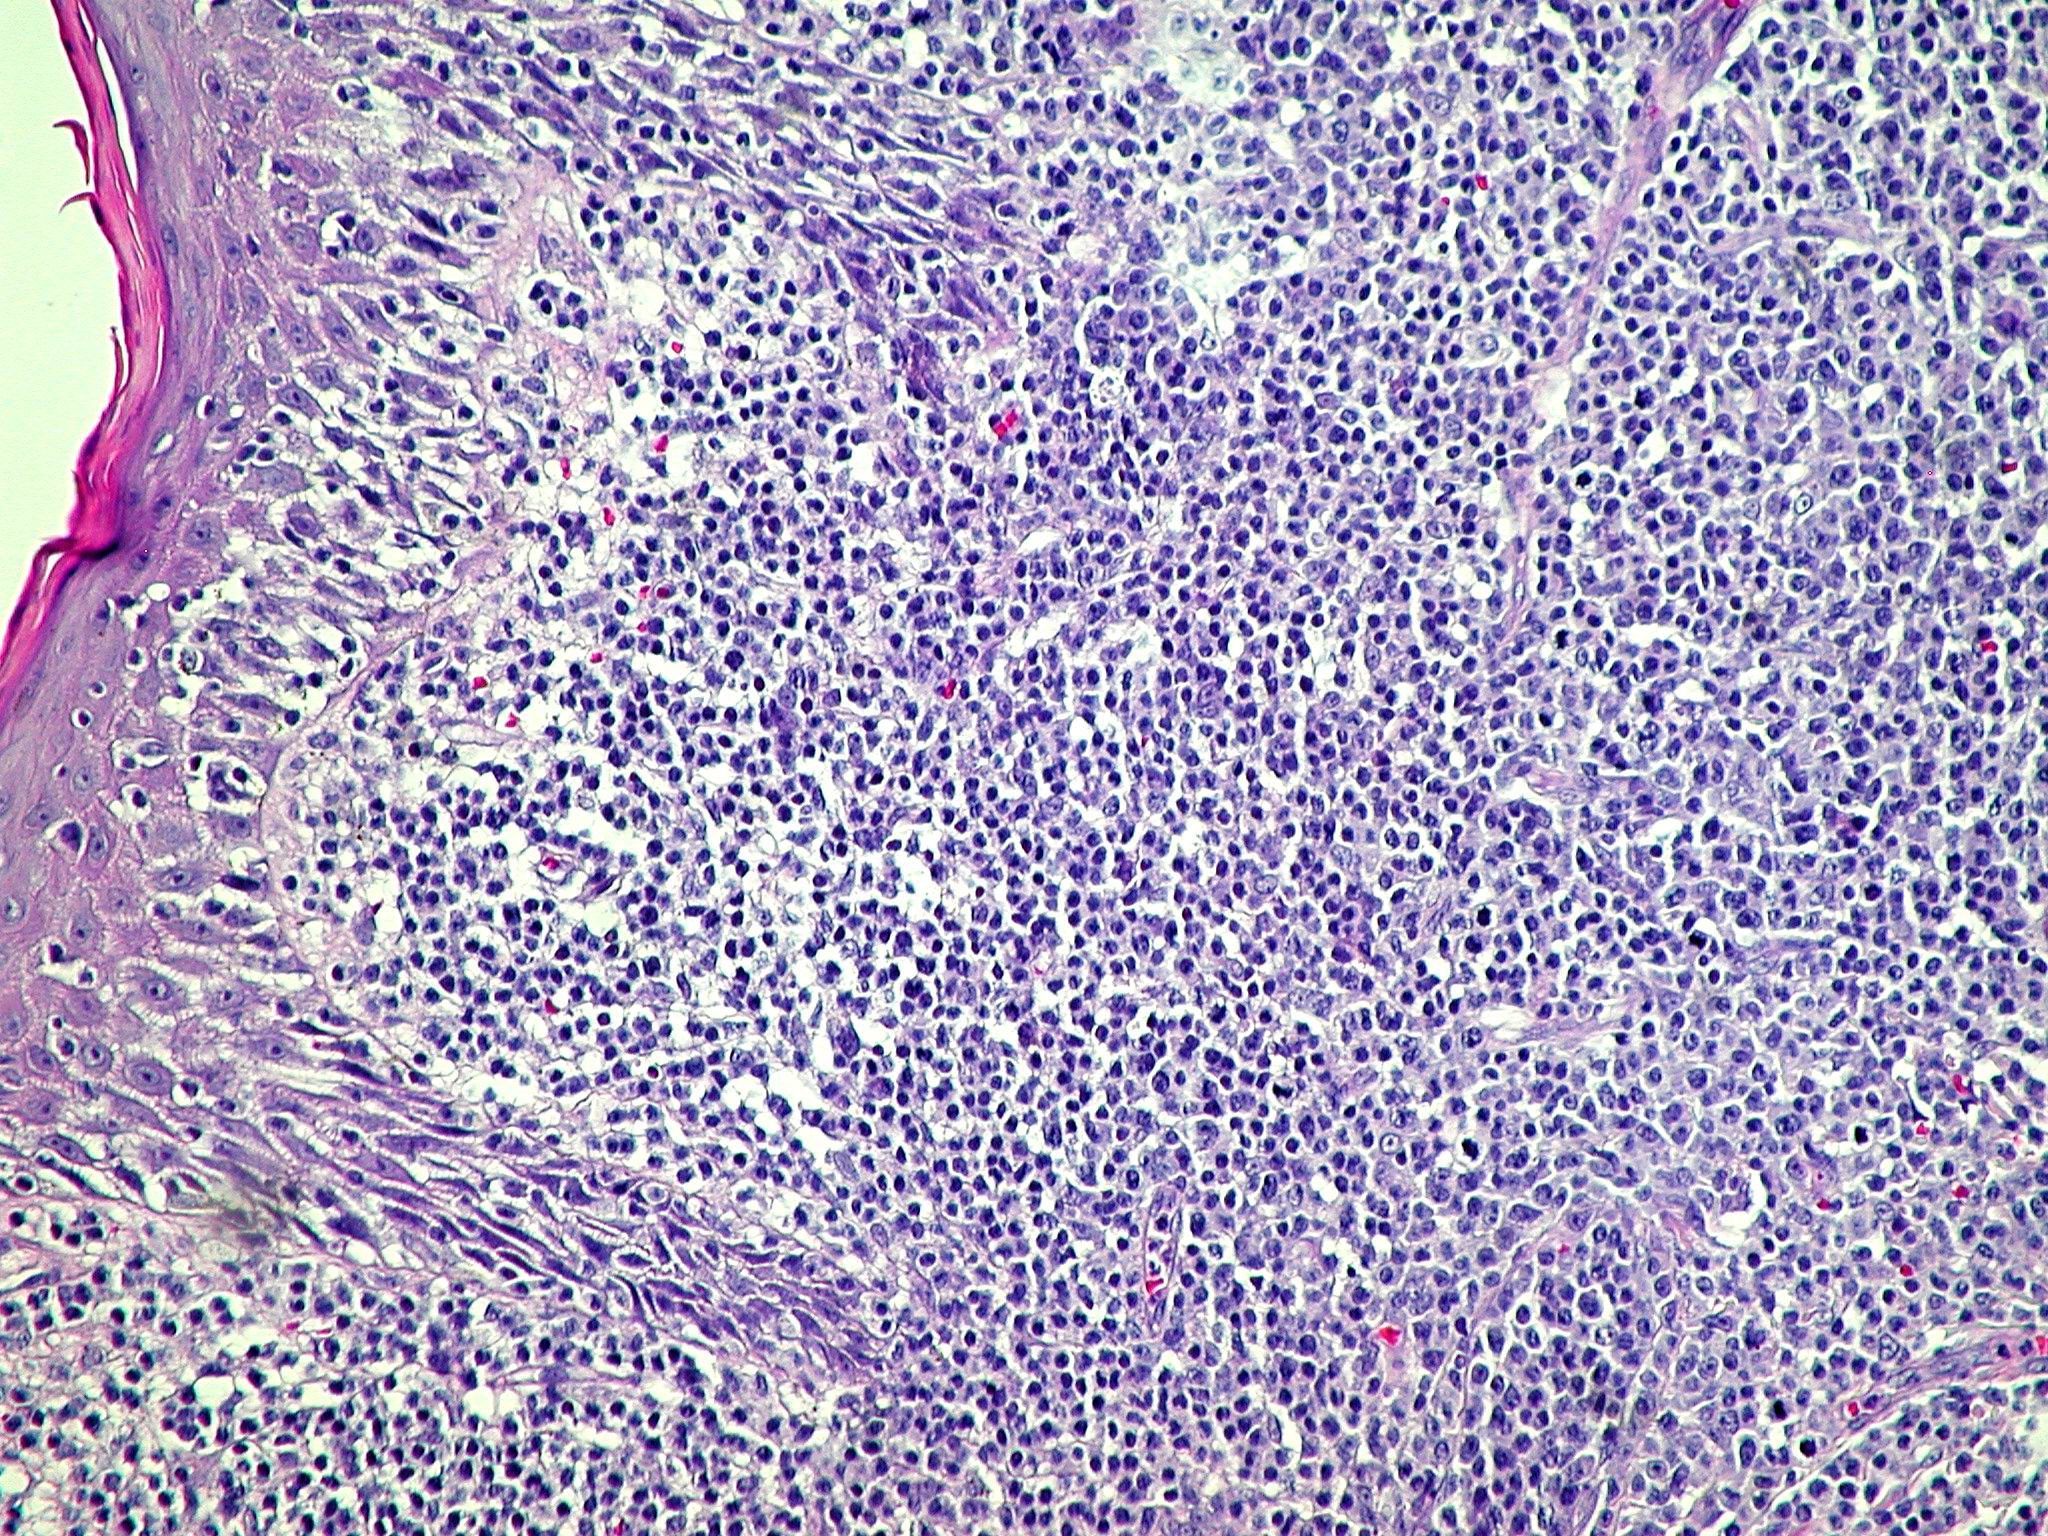

Anaplastic Large Cell lymphoma =لمفوما كبيرة الخلايا غير مصنعة